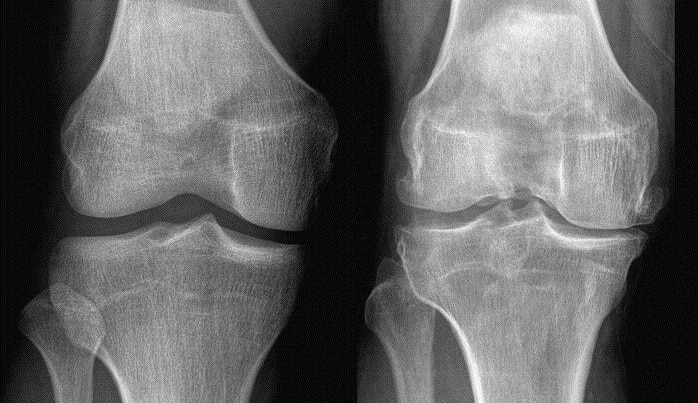

• Paziente: Uomo, 62 anni, ex sportivo, OA di grado II.

• Sintomatologia: Versamento articolare recidivante. Il paziente camminava 40 minuti al giorno nonostante il dolore, convinto che “bisogna soffrire per migliorare”.